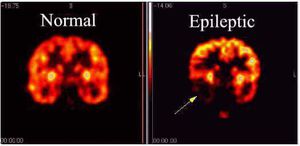

Epilepsy is a common and diverse set of chronic neurological disorders characterized by seizures Some definitions of epilepsy require that seizures be recurrent and unprovoked, but others require only a single seizure combined with brain alterations which increase the chance of future seizures. In many cases a cause cannot be identified; however, factors that are associated include brain trauma, strokes, brain cancer, and drug and alcohol misuse among others.. Epileptic seizures result from abnormal, excessive or hypersynchronous neuronal activity in the brain. The diagnosis of epilepsy usually requires that the seizures occur spontaneously. Nevertheless, certain epilepsy syndromes require particular precipitants or triggers for seizures to occur. These are termed reflex epilepsy. For example, patients with primary reading epilepsy have seizures triggered by reading. Photosensitive epilepsy can be limited to seizures triggered by flashing lights. Other precipitants can trigger an epileptic seizure in patients who otherwise would be susceptible to spontaneous seizures. For example, children with childhood absence epilepsy may be susceptible to hyperventilation. In fact, flashing lights and hyperventilation are activating procedures used in clinical EEG to help trigger seizures to aid diagnosis. Finally, other precipitants can facilitate, rather than obligately trigger, seizures in susceptible individuals. Emotional stress, sleep deprivation, sleep itself, heat stress, alcohol and febrile illness are examples of precipitants cited by patients with epilepsy. Notably, the influence of various precipitants varies with the epilepsy syndrome. Likewise, the menstrual cycle in women with epilepsy can influence patterns of seizure recurrence. Catamenial epilepsy is the term denoting seizures linked to the menstrual cycle.